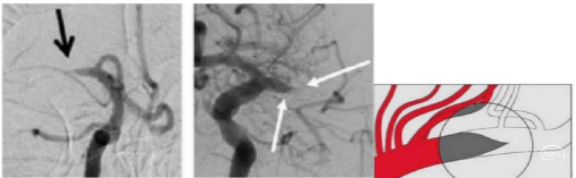

七、轨道征

轨道征是指大动脉血栓周围存在一条或两条造影剂通道。研究表明,轨道征患者可能通过动脉溶栓或静脉溶栓再通。轨道征不代表责任血管完全闭塞,而是代表着存在完全闭塞的趋势。

八、锥形征象

每一台血管内介入取栓都是一场迅速集结应对的“遭遇战”。只有储备大量的介入知识信息,做好术前材料准备,掌握规律,才能因病施治。